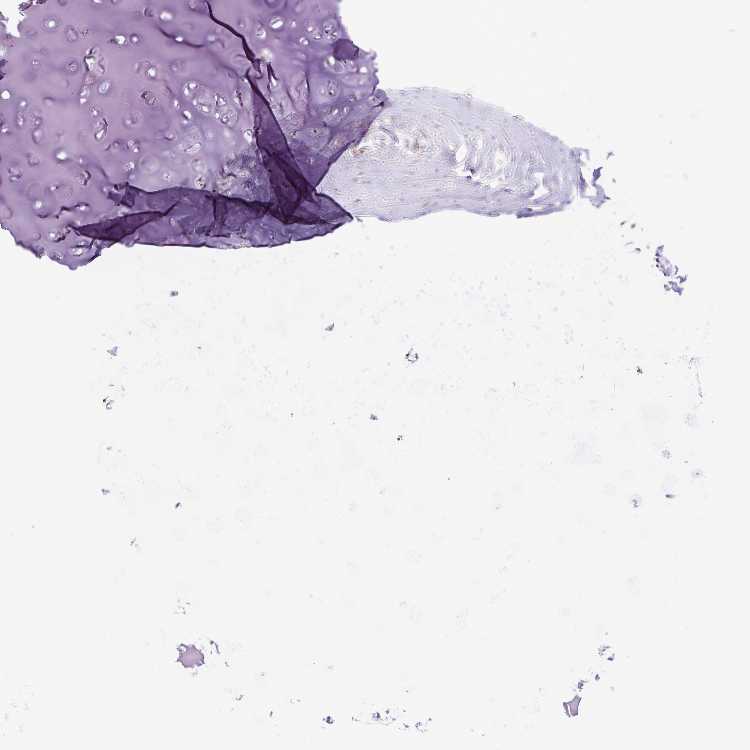

ADIPOSE TISSUE - Antibody stainingi

Antibody staining in the annotated cell types in the current human tissue is reported as not detected, low, medium, or high, based on conventional immunohistochemistry profiling in selected tissues. This score is based on the combination of the staining intensity and fraction of stained cells.

Each image is clickable and will lead to virtual microscopy that enables deeper exploration of all samples and also displays staining intensity scores, fraction scores and subcellular localization as well as patient and tissue information for each sample.

Antibody HPA062681

Adipocytes Not detected